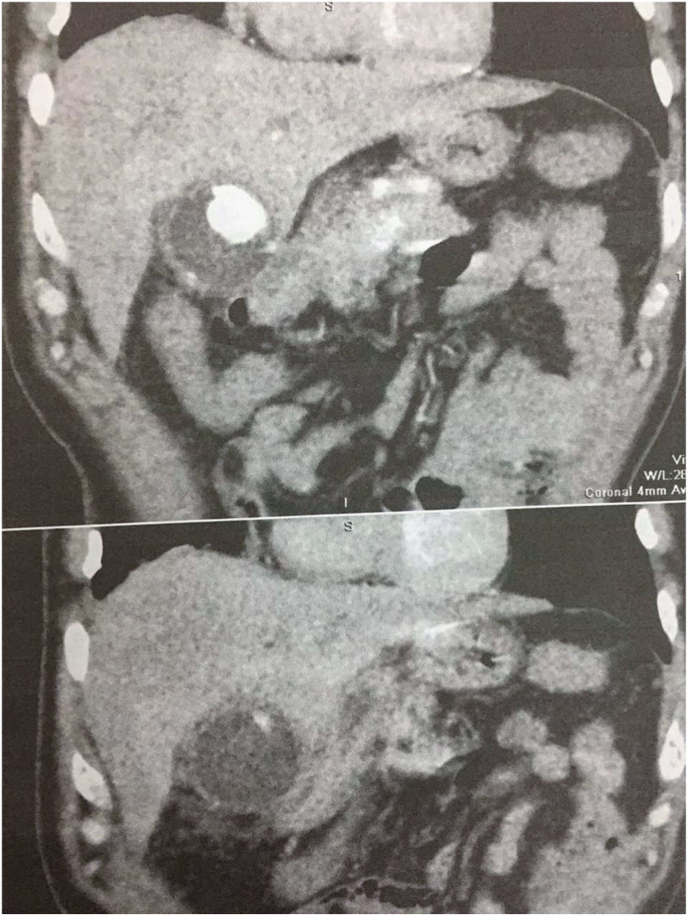

An abdominal CT was performed, revealing a dilation in CBD (1 cm). Inside the gallbladder, a 13 × 5 cm cystic mass was detected too.

A gallstone was found as well.

Those entities applied pressure on the beginning of the CBD. The potential diagnosis was a hydatid cyst of the gallbladder.

When it comes to symptoms, it is known that cysts grow slowly over years before they cause any clinical symptoms, this is mainly true regarding relatively large organs such as the liver. However, since our case is an intraluminal cyst in the gallbladder, it takes less time compared to other locations to be clinically explicit [ref. 8]. (Fig. 3)

In our case, we conducted an USG, and following the discovery of daughter cysts, an abdominal CT was conducted, and from its findings, we were able to diagnose the disease (Fig. 4)

In our case, laparoscopic surgery was chosen, mainly because of the low spillage possibility and the expertise of the surgeon (Fig. 4). Overall, PGBHC is a very rare entity that is found in the agricultural areas, most likely diagnosed by USG and CT, and surgery is always the indicated upon diagnosis.